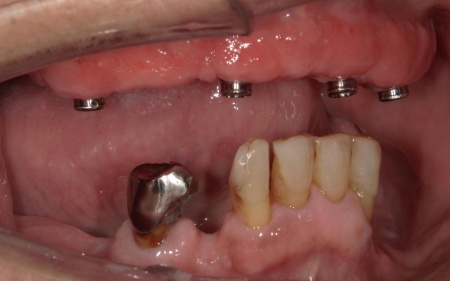

傷が治り、インプラントが顎の骨にしっかりと結合したことを確認したら、インプラントの頭部分に入れ歯と連結するための部分となる「アタッチメント」を装着しました。

次に、上顎には「インプラント支持型義歯(インプラントオーバーデンチャー)」を金属床義歯で作製します。

また、下顎は保険診療の部分入れ歯を再作製し、上下の噛み合わせの回復を図りました。